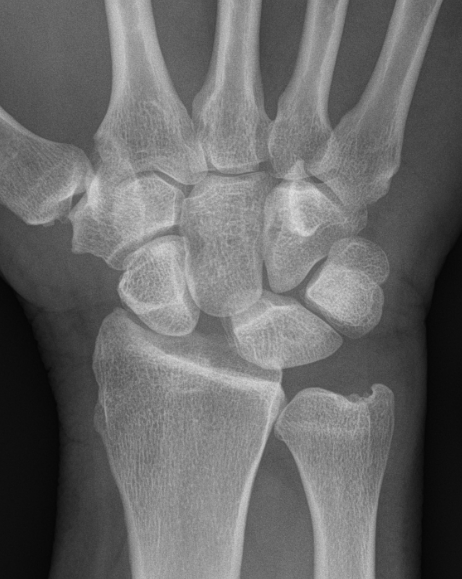

X-ray

Scapholunate gap > 3 mm

AP

| Terry Thomas sign | Cortical ring sign | Scaphoid shortened |

|---|---|---|

|

Increased scapholunate interval > 3 mm compared with other side |

End on view of distal scaphoid due to flexion | Shortened due to flexion |